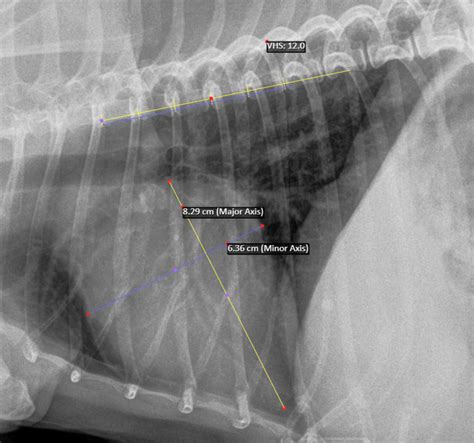

Vertebral Heart Score. Web idexx web pacs can generate a vertebral heart score (vhs) instantly and automatically using artificial intelligence.

Web idexx web pacs can generate a vertebral heart score (vhs) instantly and automatically using artificial intelligence.